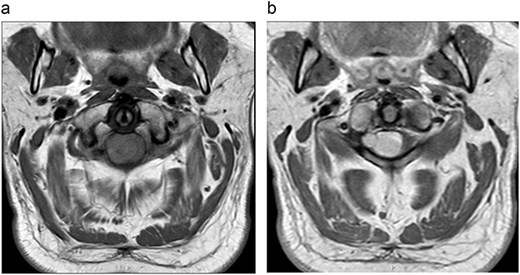

Post-operative MRI done 6 weeks following the procedure demonstrated near total resection of the intradural extramedullary tumour with small component of tumour seen along the exiting right C2 nerve root. There is complete resolution of mass effect of the spinal cord at C2 level.